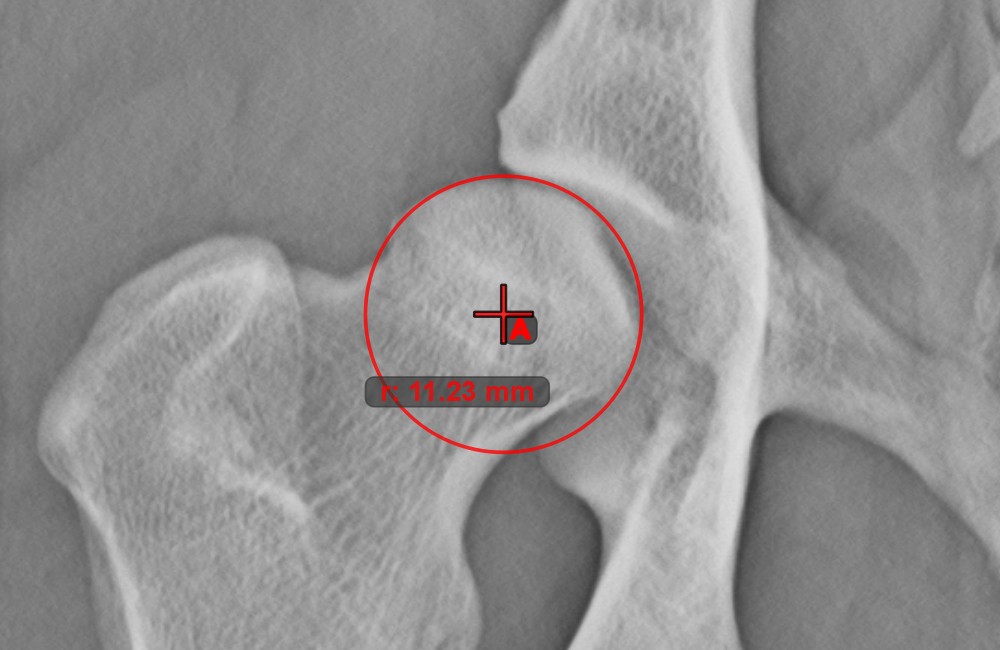

Circle from 3 Points¶

The Circle from 3 Points tool is a simple and effective way to create a circle from just three points.

Start by selecting the tool from the left toolbar and assign it to one of the available mouse buttons. Place the three points of the circle, or select the points from ones available on the scene. The circle will be automatically created based on the position of the three points. The origo of the circle will always be marked with O. The radius of the circle is automatically calculated.

Modify the position of the three points to change the radius of the circle by using the Select/Move Item tool.